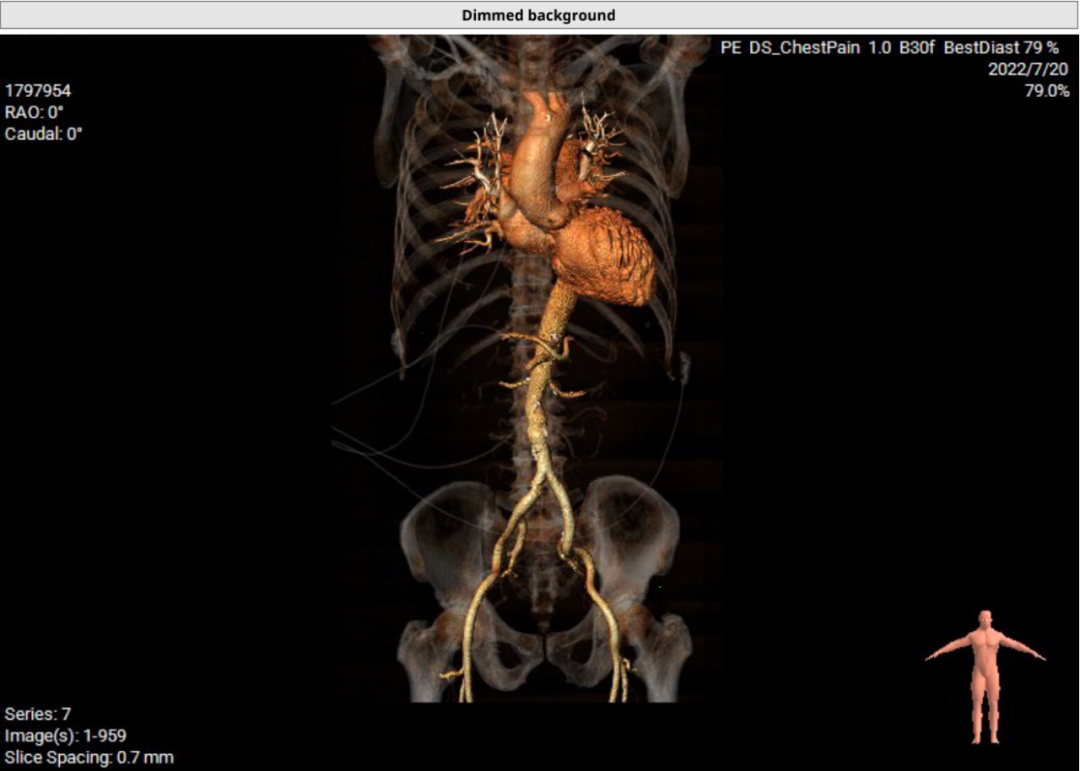

患者64岁男性,Type 0 型二叶瓣、横位心。主动脉瓣中度狭窄,重度反流,瓣环周长92.0mm,平均径29.0mm。LVOT周长98.7mm,升主扩张,窦部结构极限,锚定能力极限。入路两侧血管轻度迂曲,分叉高度可,两侧血管内径均>8mm。

患者左、右冠高度,瓣叶长度,窦宽相对瓣膜均尚可,冠脉风险低。但由于患者重度AR,可能因植入深度和选择大型号瓣膜,带来较高的传导阻滞风险。其次,患者升主扩张,存在破裂风险。最后,患者是横位心,瓣环及流出道结构大,术中瓣膜释放的位置达到了极限,瓣膜释放后可能会发生位移,有瓣中瓣风险。

术中,通过预塑形导丝送入左室,主动脉根部造影反流,延大鞘进入输送系统,定位输送系统位置,瓣膜释放1/3时,起搏160bpm,快速释放至3/4处,瓣膜正常工作,手术顺利完成。